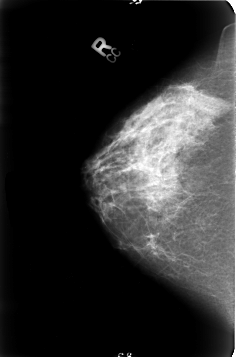

B_3023_1.LEFT_CC

LEFT_CC LINES 4696 PIXELS_PER_LINE 3072 BITS_PER_PIXEL 12 RESOLUTION 50 OVERLAY

RIGHT_CC LINES 4632 PIXELS_PER_LINE 3056 BITS_PER_PIXEL 12 RESOLUTION 50 NON_OVERLAY